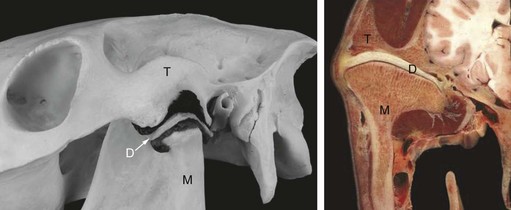

Identifying arthritis of the TMJ radiographically is often difficult, and other methods of imaging the joint, such as ultrasonography or scintigraphy, may be more useful. Ultrasonographic features of an arthritic TMJ include an irregular contour to both the temporal and mandibular components of the joint and an abnormally large volume of synovial fluid (Fig. 23.3). Typical scintigraphic findings include a mild to moderate increase in radiopharmaceutical uptake over the affected joint compared to the unaffected, contralateral TMJ. Arthrocentesis of the arthritic TMJ yields synovial fluid that is less viscous than normal and that has a normal nucleated cell count and a normal or mildly elevated concentration of protein. Proliferative new bone formation and cartilage loss are features observed during arthroscopic examination of the joint (Fig. 23.4).

Fig. 23.3 Ultrasonograms of a horse with osteoarthritis of the left TMJ. The right TMJ is normal, whereas the left has extensive formation of new bone at the surface of the joint, joint effusion, and thickening of the joint capsule. T, temporal bone; M, mandibular bone; D, intra-articular disc.

Ultrasonographic examination of the TMJs is easily performed with the horse standing and is usually well tolerated by the horse.7,34 To obtain optimal quality of the image, hair over the TMJ to be examined should be clipped, but the procedure can sometimes be performed adequately without clipping the hair. The area is cleansed and covered with a coupling gel. Both TMJs should be examined for comparison. A 7.5 MHz (or higher) linear array transducer provides sufficient depth to image the TMJ, while still providing excellent resolution of the images.

The ultrasonographic examination allows evaluation of the bony surfaces of the joint, the fibrocartilagenous disc, and the joint capsule, and quantification of the amount of synovial fluid within the joint. The surface of the bones should appear as smooth, hyperechogenic lines. The disc appears as a homogenous wedge, the base of which is located laterally and the apex of which points medially, between the surface of the zygomatic process of the temporal bone and the surface of the mandibular condyle and is similar in echogenicity to the menisci in the stifle. The caudal recess of the discotemporal compartment of the TMJ is filled with synovial villi and is difficult to distinguish ultrasonographically from the disc. The joint capsule is visible as an interface between the disc and the parotid salivary gland, which overlies it on the caudal part of the joint, or subcutaneous tissue, which overlies it on the rostral part of the joint. No synovial fluid, or only a very minimal amount, is visible if the TMJ is normal. Changes in the TMJ seen ultrasonographically that are pathognomonic for disease of the joint include irregular outline of the bony surfaces, increased amount of synovial fluid, hyperechogenicity of the synovial fluid, disruption of the homogenous appearance of the disc, or thickening of the joint capsule (Fig. 23.3).